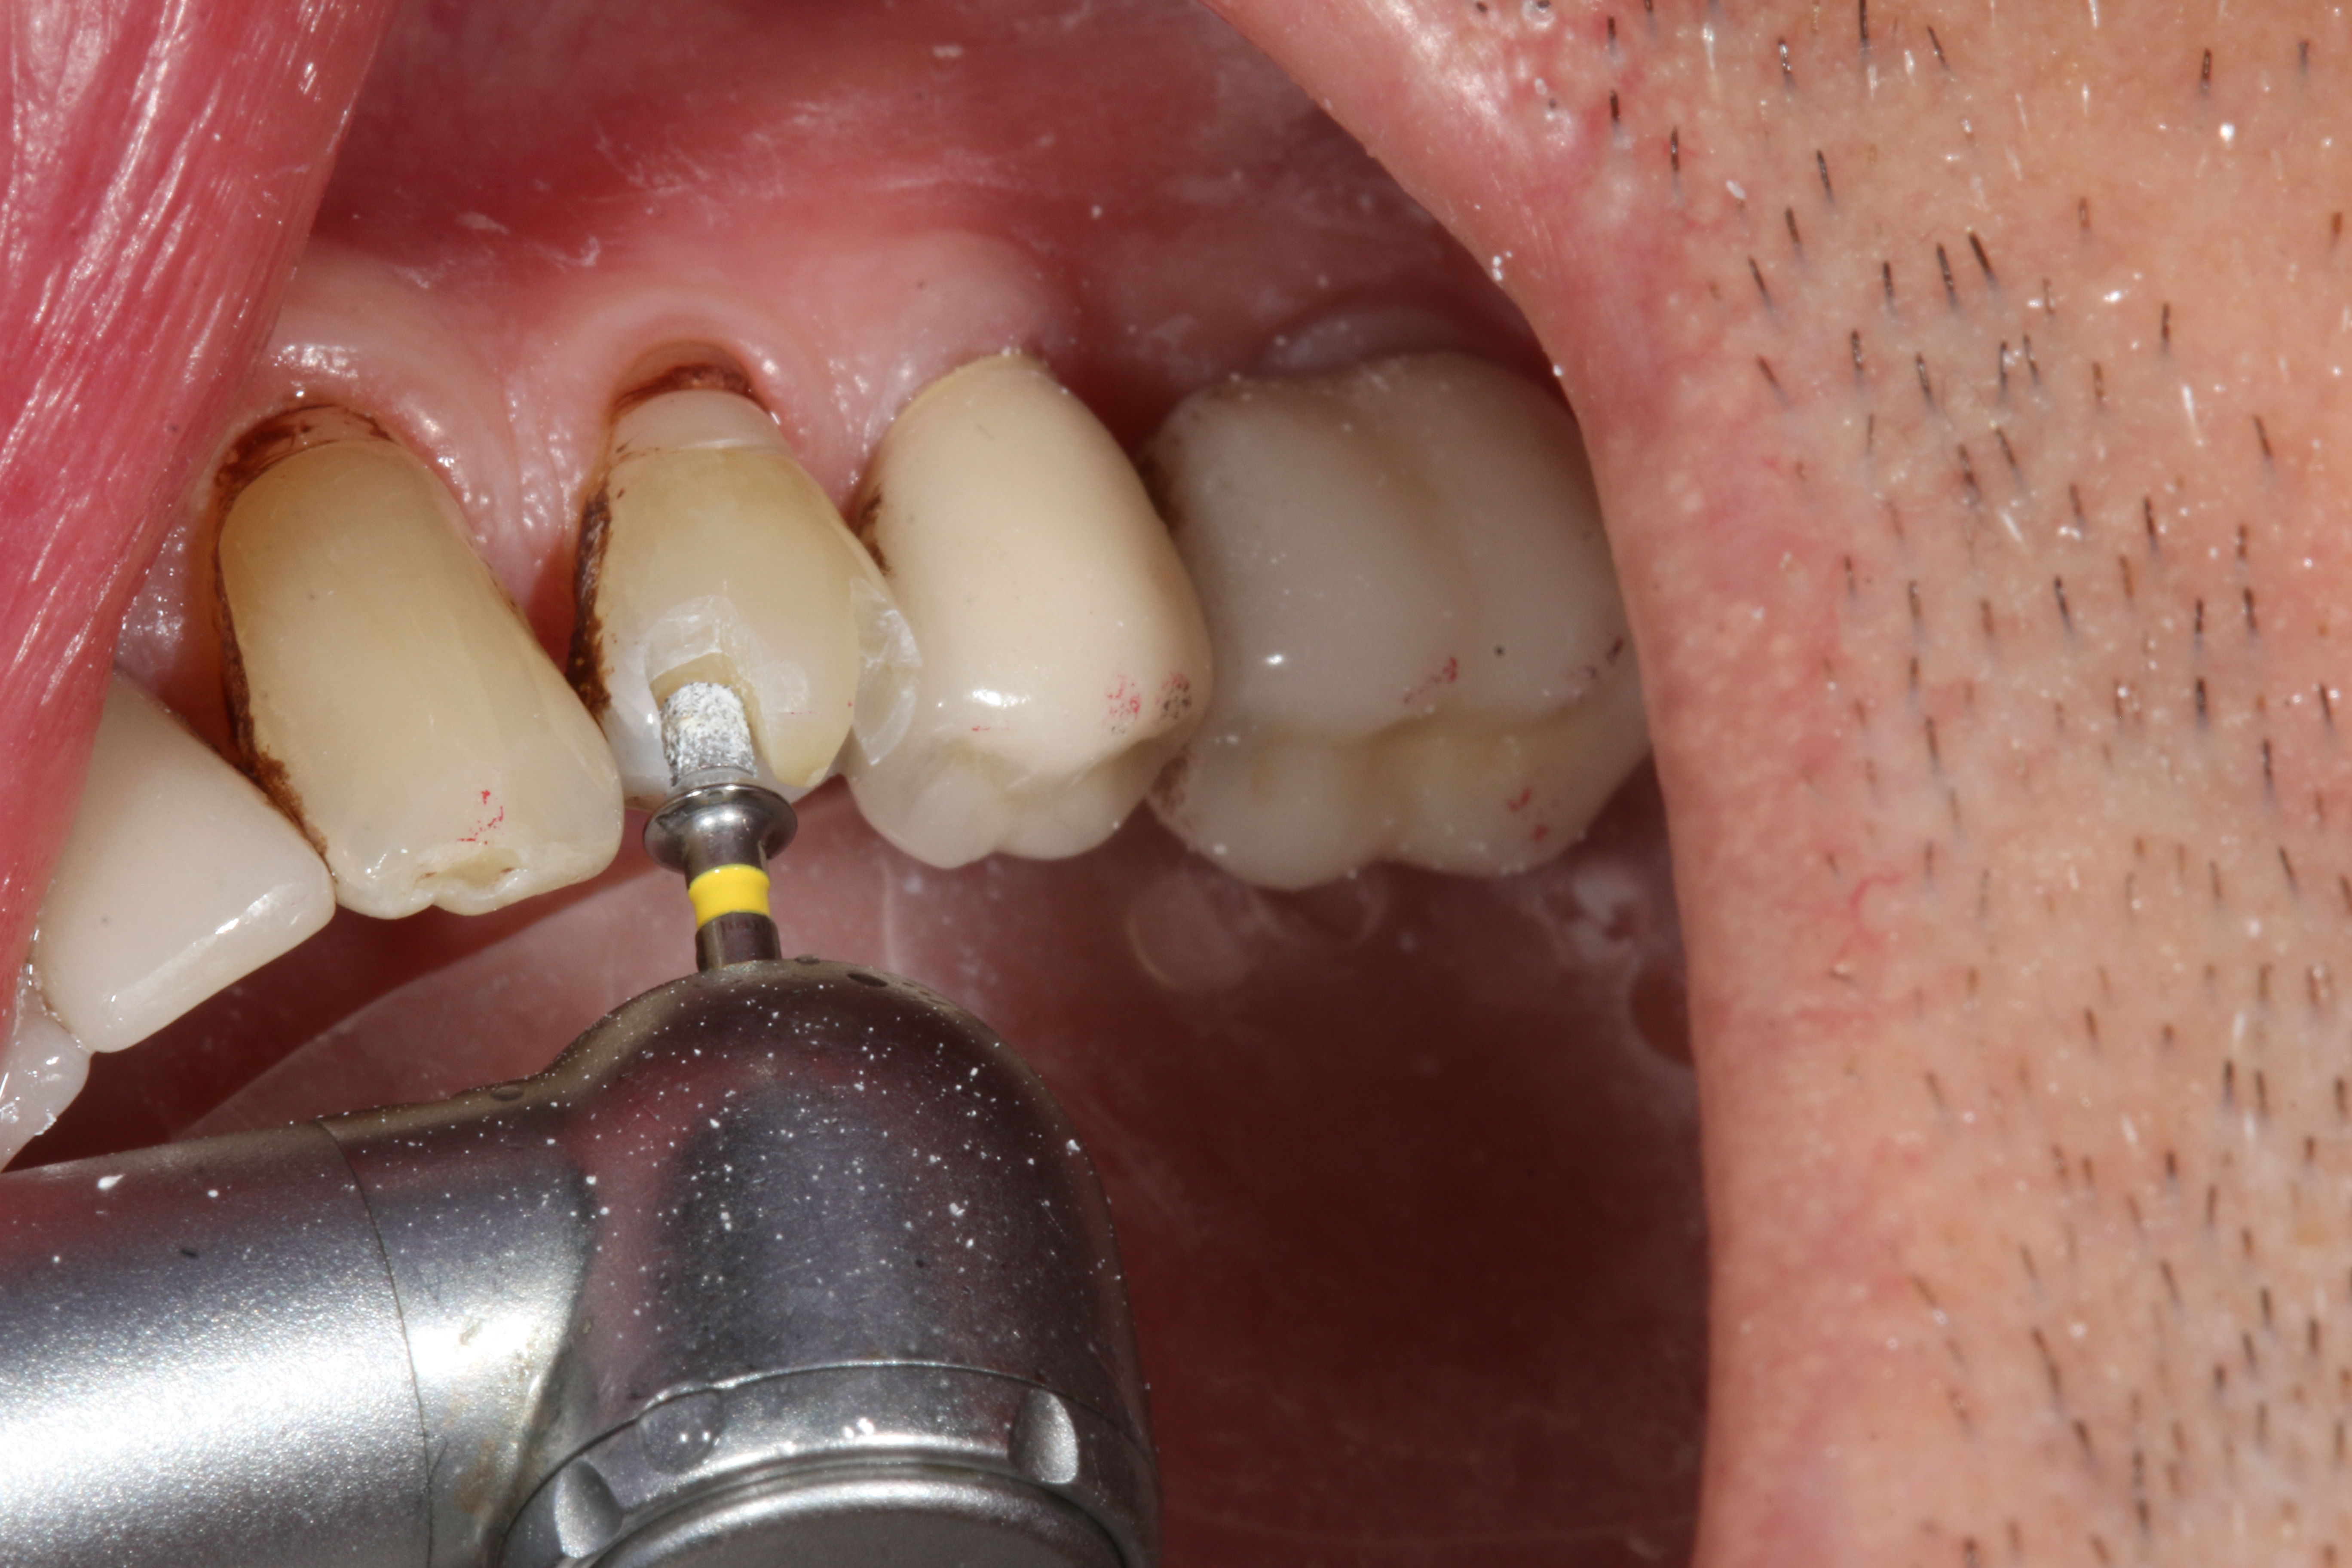

CAD/CAM dentistry is very precise. For accuracy, the preoperative, shade, bite, and upper/lower tooth scans are best taken before anesthesia and dental procedures that induce muscle fatigue (Figure 3). After infiltration anesthesia with 1 carpule of articaine hydrochloride 4% and epinephrine 1:100,000 injection, the temporary was removed. Occlusal reduction of 2.0 mm was precise and defined with an 828Y depth cutting bur to meet restorative requirements (Figure 4), and the post space was restored. Axial reduction and shoulder margination were performed with a coarse KS1 bur. After smoothing of the preparation, a 15% aluminum chloride topical gingival retraction paste was injected and compressed into the sulcus, then thoroughly rinsed with water and air-dried, before scanning of the tooth preparation and critical adjacent anatomy (Figure 5 and Figure 6).

Fig 4. Depth cutting allows precision reduction to avoid overreduction and compromise of restorative strength.

Figure 4